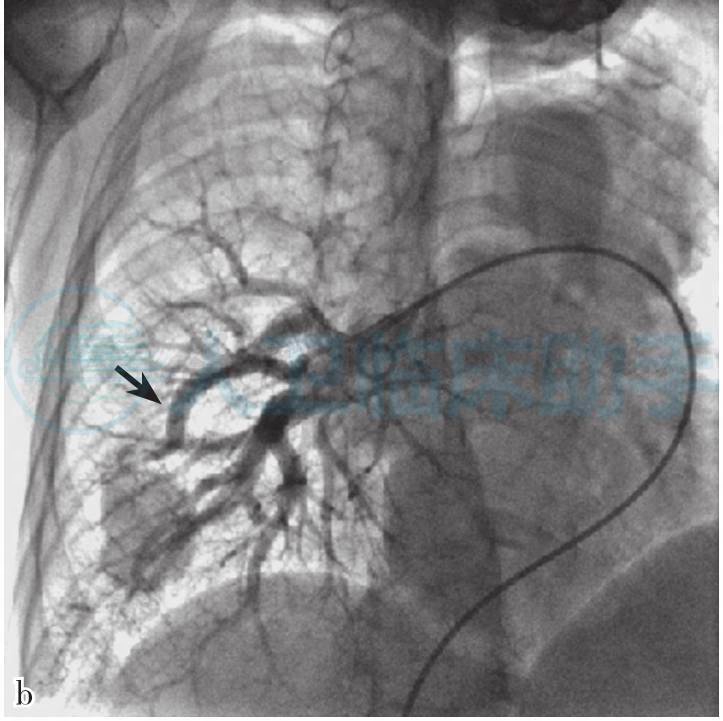

左、右肺动脉发育良好;左上肺动脉前支扩张,与一巨大瘤囊相通,瘤囊内造影剂经左上肺静脉回流至左心房。右中肺动脉发出一迂曲、扩张的分支与另一巨大的瘤囊相通,瘤囊内造影剂经右上肺动脉回流至左心房(图2)。

图2 肺动脉造影:a.左上肺动脉前支扩张(箭头所示),与一巨大瘤囊相通;b.右中肺动脉发出一迂曲、扩张的分支与另一巨大的瘤囊相通(箭头所示为供血血管)